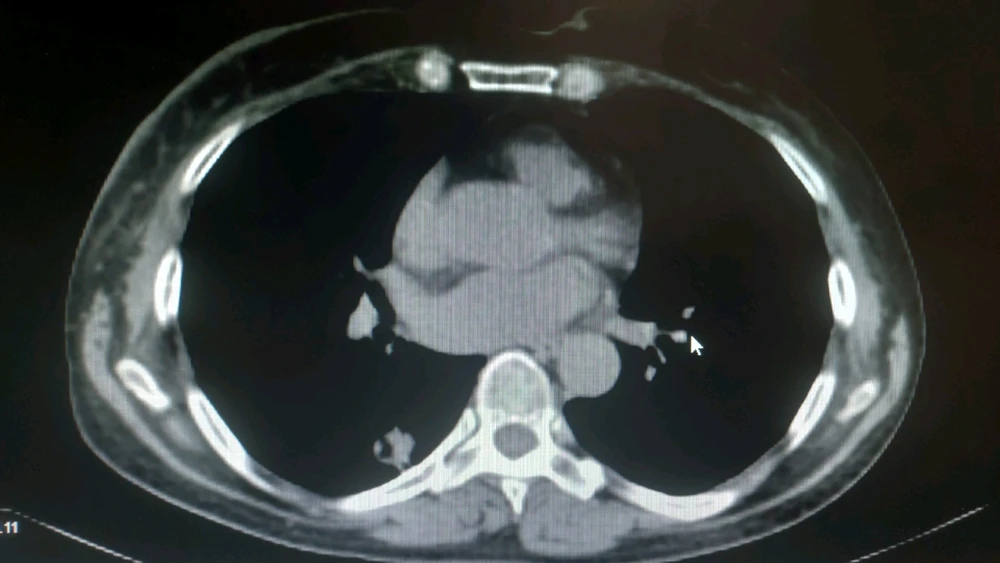

Nodulo pulmonar solitario en segmento superior de lóbulo inferior derecho (LID). A esto en radiología se le puede llamar de varias maneras, por ejemplo condensación pulmonar con bronquio abierto (el puntito negro que se ve en la imagen más blanca) en contacto con pleura (está pegada a pared... leer más